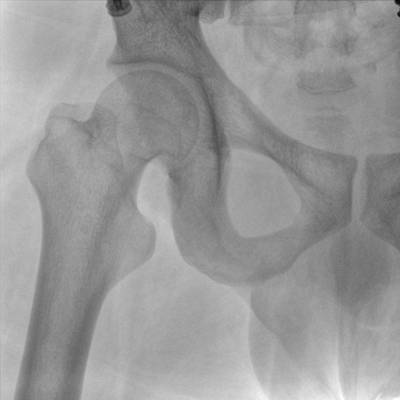

Clinical picture

臨床圖片